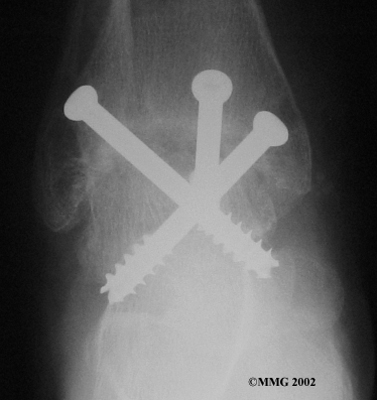

When the ankle joint becomes so painful that it is difficult to walk, surgery may be suggested to fuse the ankle joint. An ankle fusion is sometimes also called an ankle arthrodesis. In this operation, the three bones that make up the ankle joint (the talus, the tibia, and the fibula) are allowed to grow together, or fuse, into one bone. Once this is done the ankle no longer is able to move, but with a successful fusion the pain is gone. Most people with a successful fusion of the ankle are able to walk without much trouble, and in some cases it is almost impossible to tell that the ankle is stiff. But it is very difficult to run because you lose the ability to push off with the toes. The foot can't bend down.

Ankle Fusion

Most people will need some changes made to their shoes following an ankle fusion. Because the ankle no longer moves, it is difficult to roll over the top of the foot when you take a step. For this reason, shoes are usually fitted with a rocker sole. This allows the shoe to roll instead of the foot. A special heel is sometimes built on the shoe to absorb some of the shock.

The ankle fusion is a good operation, especially for a young, active person. It is usually the preferred option for post-traumatic arthritis of the ankle. Once the ankle is successfully fused it can last a lifetime, and no other operations are expected later unless there are problems. But there are complications associated with the ankle fusion, and not all ankle fusions are successful.

The biggest problem with the older artificial ankle designs is that they loosened after a relatively short time and began to cause pain. When using the newer artificial ankle designs, surgeons have tried to solve this problem by actually fusing the tibia and fibula together during the operation and placing screws across the two bones. This has dramatically increased the success rate for the artificial ankle replacements done today. Many surgeons are now beginning to use the artificial ankle for post-traumatic arthritis instead of doing a fusion. Patients are able to keep the motion in the ankle and avoid some of the problems associated with the ankle fusion.